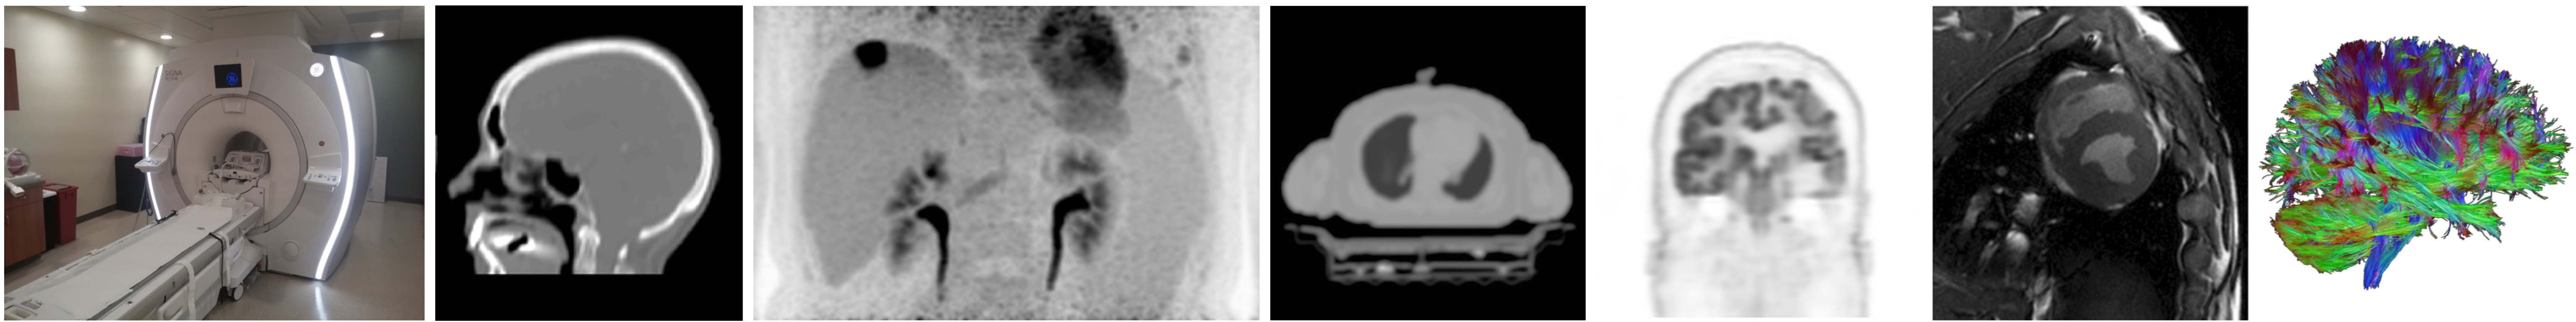

Magnetic Resonance Imaging (MRI)

We explore the frontiers of MRI technology, with a particular focus on designing and optimizing novel pulse sequences and radiofrequency (RF) coils.

- Pulse Sequence Development: Pulse sequences are patterns of RF pulses and magnetic field gradients that manipulate nuclear spins. By customizing these sequences, we can selectively highlight different tissue properties, improve image contrast, and reduce scan times.

- RF Coil Design: RF coils are essential for transmitting and receiving signals in MRI systems. We create specialized coil designs to improve signal sensitivity and overall image quality.

- Electron MRI (EMRI): Our team is developing a low-field EMRI system. EMRI detects resonance transitions of unpaired electrons, providing insights into tissue oxygenation and redox status. This approach is especially valuable for understanding hypoxia in cancer.

Positron Emission Tomography (PET)

Our PET research focuses on novel methodologies and techniques to improve sensitivity, resolution, and diagnostic utility. PET imaging involves the use of radioactive tracers that highlight metabolic processes in the body. By integrating PET with other imaging modalities, we gain a more comprehensive view of disease processes:

- PET/CT and PET/MRI: Combining PET with CT or MRI offers both functional and structural information, enhancing diagnostic accuracy.

- Methodology and Technique Development: We design advanced acquisition protocols and data analysis methods to capture more detailed information about physiological and molecular processes.